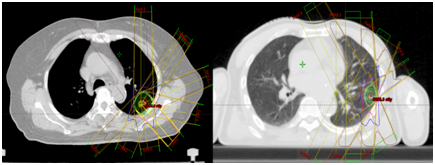

早期肺癌的SBRT治疗

科室本次引进了先进的人工智能辅助靶区勾画系统,新型的智能勾画系统相比于传统的基于图谱(Atlas-based)的自动勾画更具有优势,在放疗靶区勾画阶段可结合多模态成像对特定的靶区进行融合和配准,可精准识别病灶范围。

CT/MRI配准图像

并成功实现了复杂靶区的自动勾画,以鼻咽癌靶区勾画为例,传统手工勾画需要2-3小时,而自动勾画只需2分钟,大大简化了放射治疗的靶区勾画流程,从而缩短了患者的住院周期。

腹部和头颈肿瘤自动勾画效果